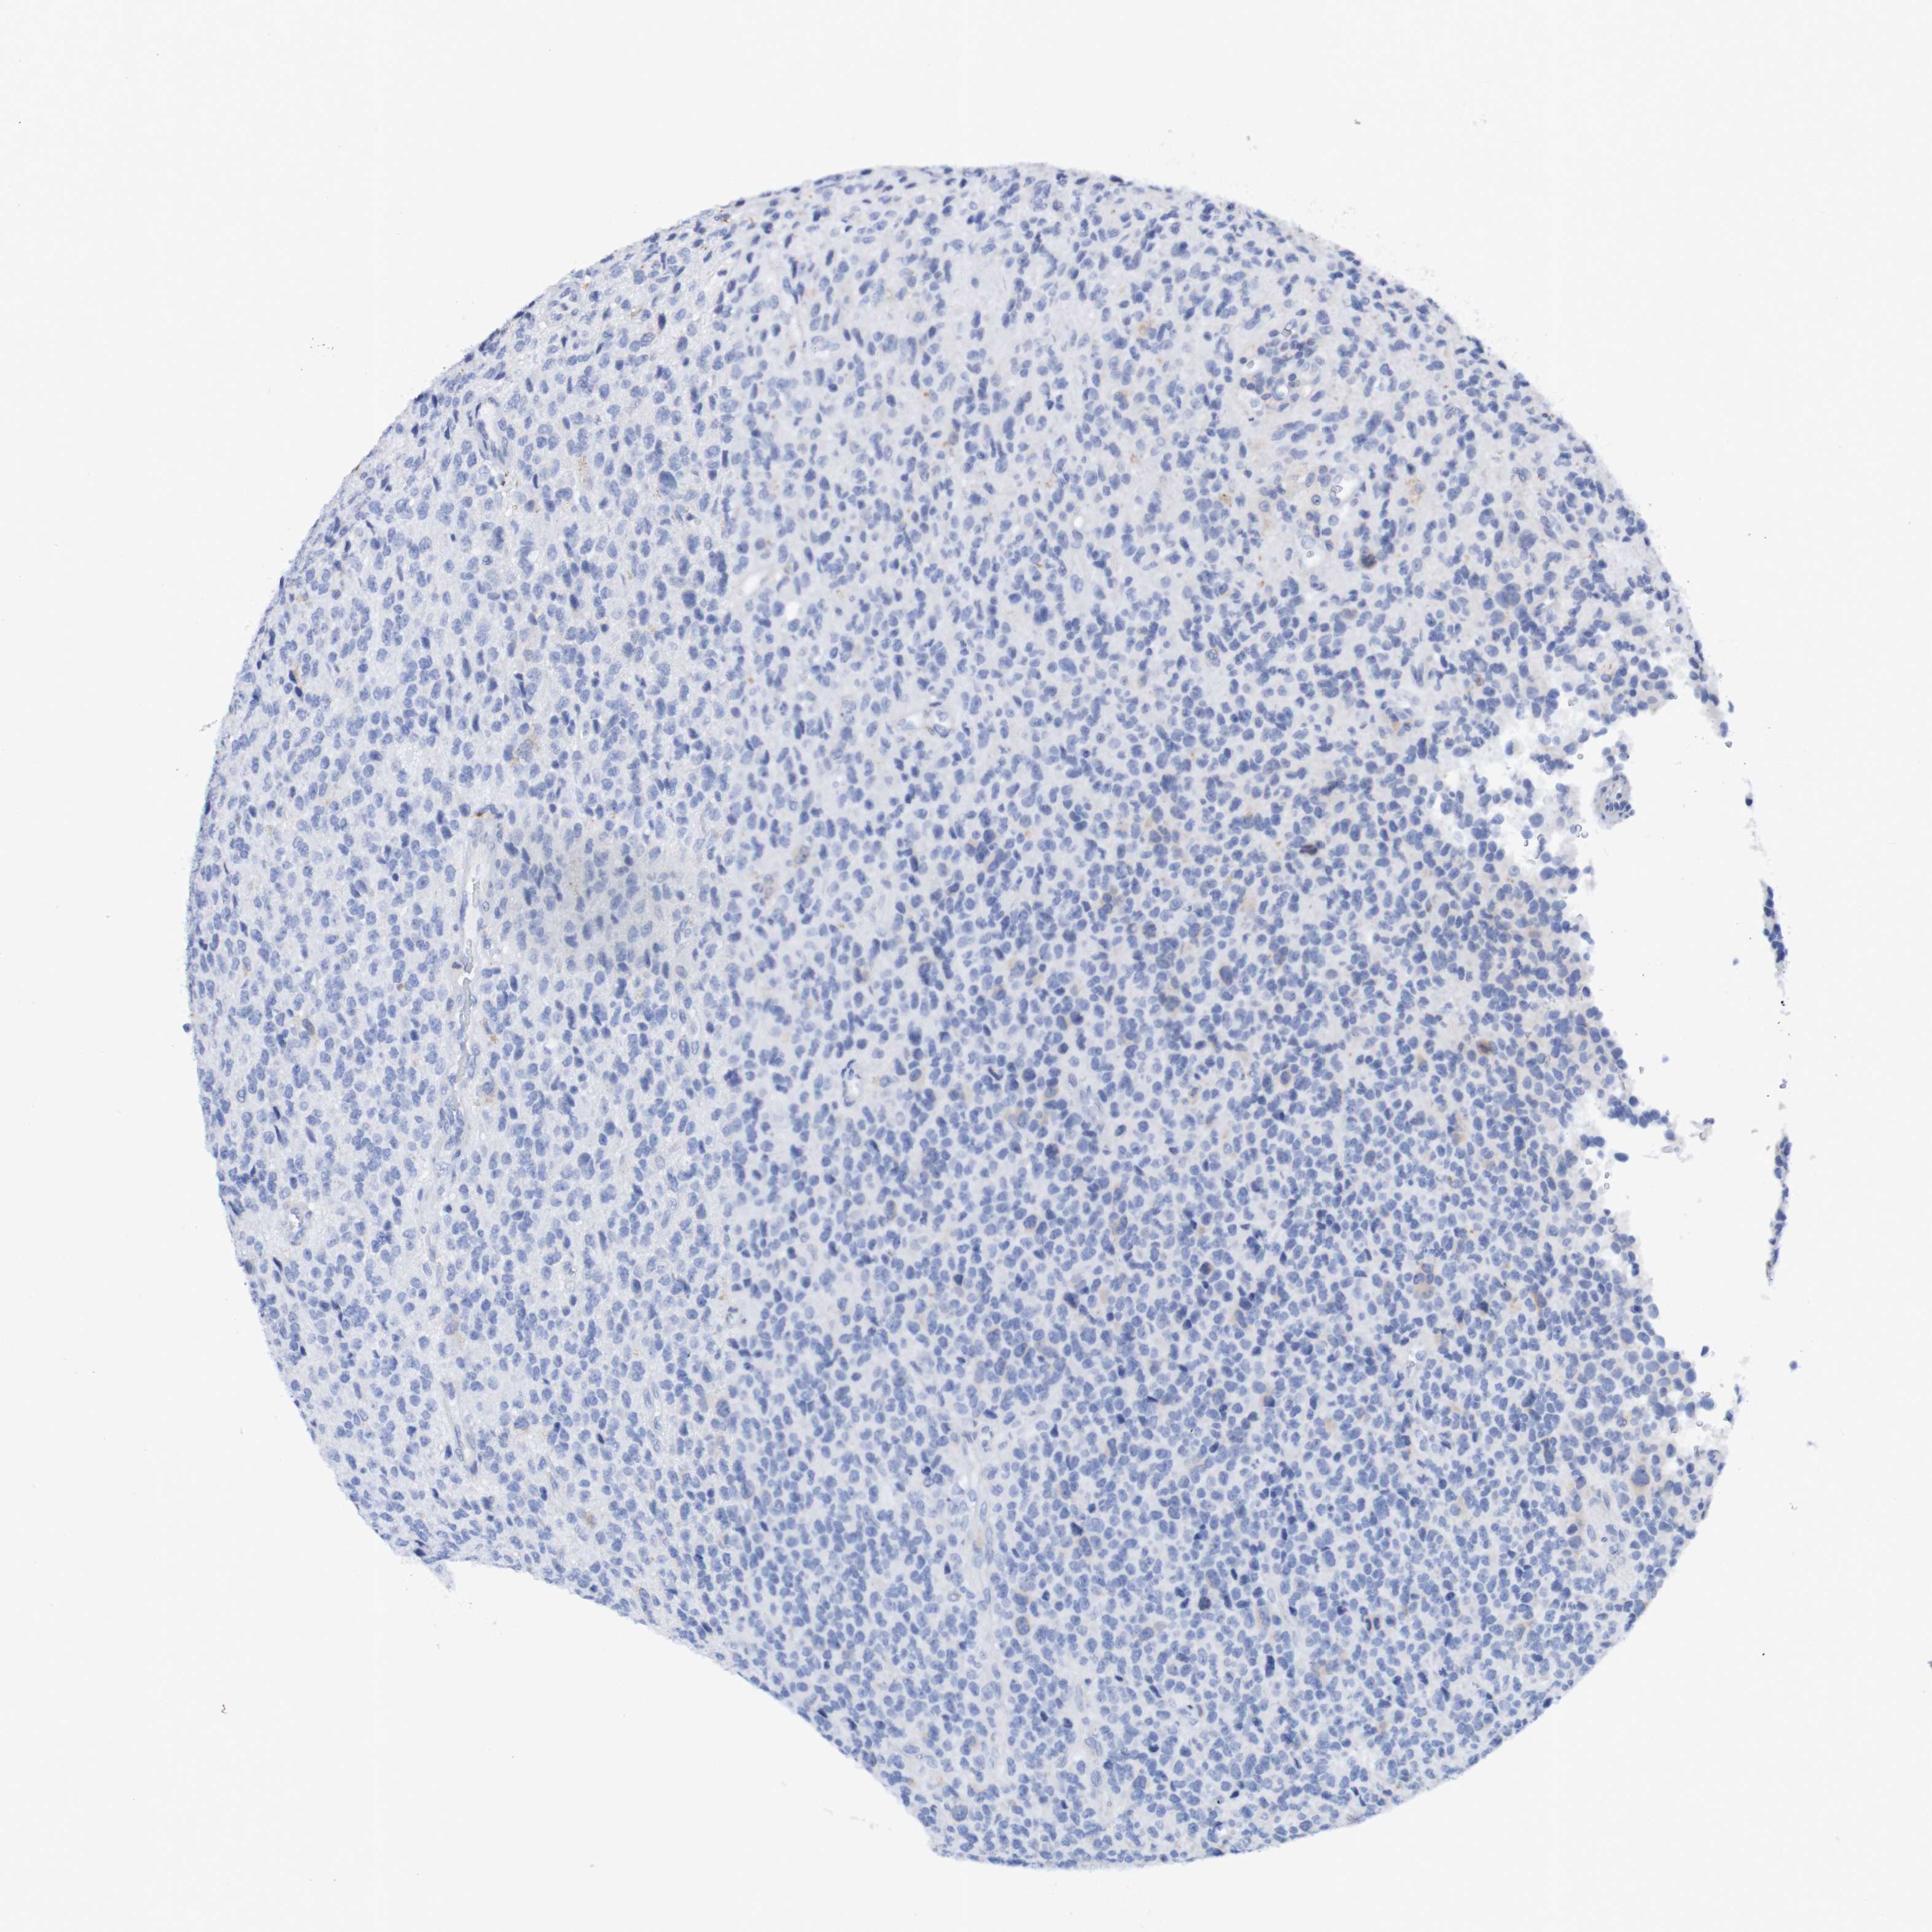

GLIOMA - Protein expressioni

A mouse-over function shows sample information and annotation data. Click on an image to view it in a full screen mode. Samples can be filtered based on level of antibody staining by selecting one or several of the following categories: high, medium, low and not detected. The assay and annotation is described here.

Note that samples used for immunohistochemistry by the Human Protein Atlas do not correspond to samples in the TCGA dataset.

Antibody stainingi

Antibody staining in the annotated cell types in the current human tissue is reported as not detected, low, medium, or high, based on conventional immunohistochemistry profiling in selected tissues. This score is based on the combination of the staining intensity and fraction of stained cells.

Each image is clickable and will lead to virtual microscopy that enables deeper exploration of all samples and also displays staining intensity scores, fraction scores and subcellular localization as well as patient and tissue information for each sample.

Antibody HPA007982

Antibody HPA011933

Staining

High

Medium

Low

Not detected

Intensity

Strong

Moderate

Weak

Negative

Quantity

>75%

75%-25%

<25%

None

Location

Nuclear

Cytoplasmic/membranous

Cytoplasmic/membranous,nuclear

Glioma, malignant, High grade

Glioma, malignant, Low grade